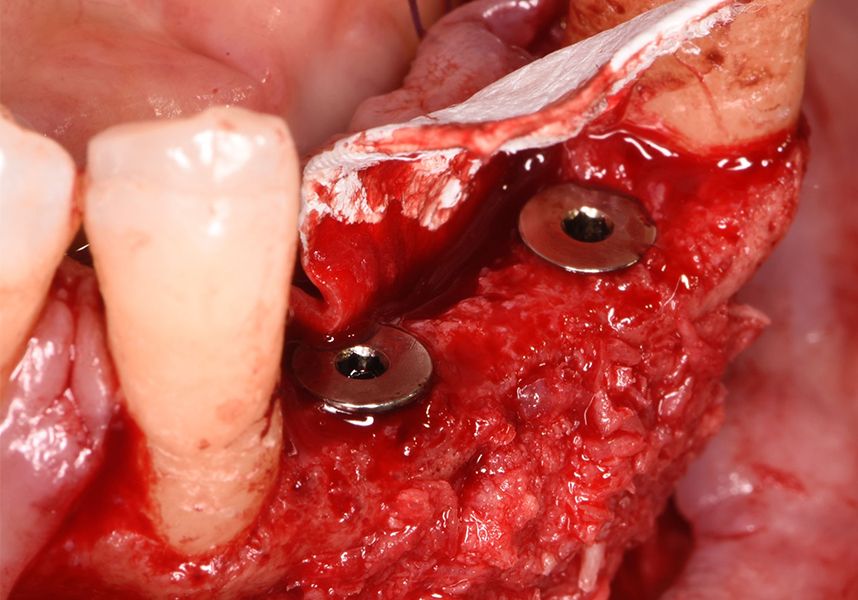

The patient was anesthetized and a flap was made from the distal area of tooth 43 up to 36. Then two Avinent Biomimetic Ocean IC implants of 3.5x10 were inserted in positions 32 and 42.

Respecting the three-dimensionally correct position of the implant led to bone fenestration, leaving the apical part of the apex of the implant exposed almost to the mid-point of its length at 42 and a third in 32.

To treat the defect, bone regeneration was carried out simultaneous to the surgical process, with an autologous bone graft from the patient. In the internal part of the graft we used autologous cortical bone obtained by scraping (Safescraper) and from the biological drilling, at low revolutions and without irrigation, from the other implant beds. In the external layer of the regeneration we used a xenograft (Genoss, Osteogenos) and this was covered with a reabsorbable collagen barrier membrane (Evolution STD, Osteogenos).